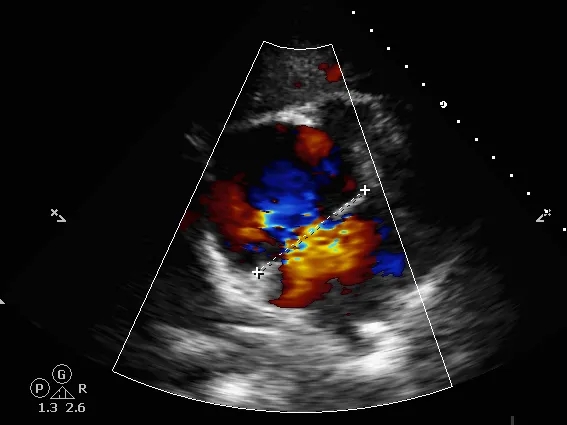

锁定后评估

心尖四腔心切面可见封堵器形态良好

主动脉短轴切面可见封堵器呈“Y”字型抱住主动脉

彩色多普勒血流成像显示无残余分流存在